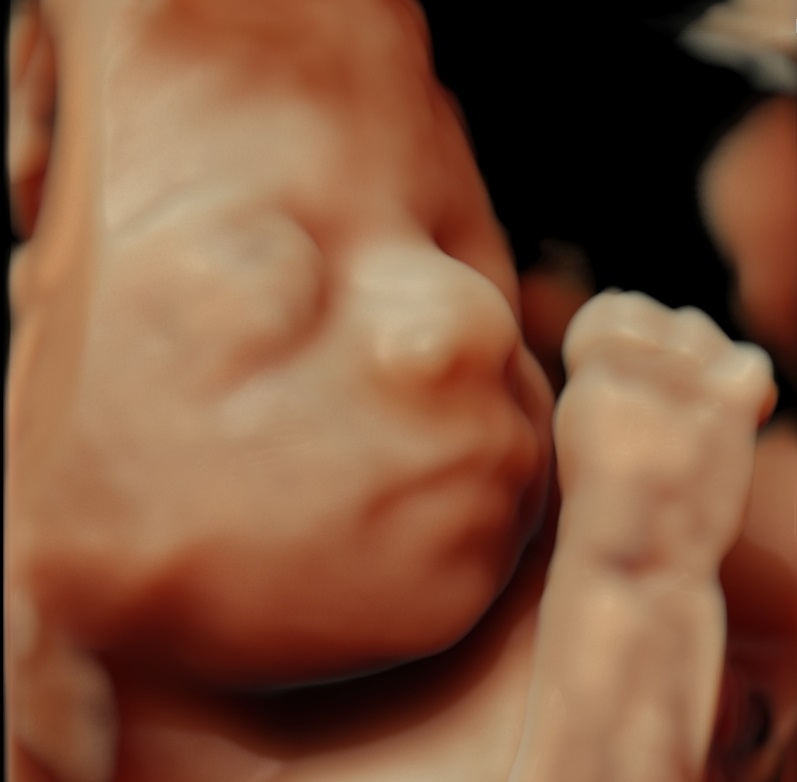

Φωτογραφίες από το αρχείο και από το χώρο του ιατρείου του γυναικολόγου Βυθούλκα Κωνσταντίνου, καθώς και του εργαστηρίου της κυτταρολόγου Λιβέρη Κατερίνας.